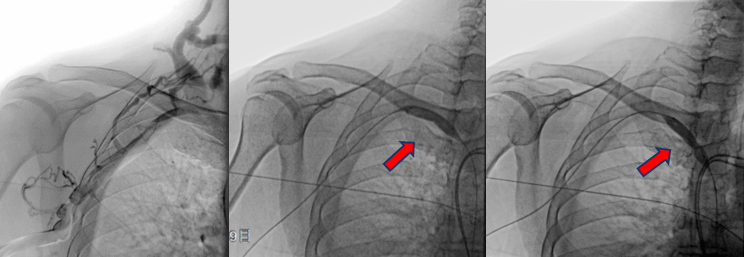

病变明确了 , 张主任当机立断 , 立即进行介入手术 。 张东亮主任医师与付晨主治医师在新建成的新龙泽院区介入手术中心进行了局麻下经皮穿刺血管内介入治疗 。 张主任凭借丰富的经验、娴熟的手法很快将超滑导丝通过病变部位 , 10mm高压球囊将狭窄部位扩张至无回弹 , 再次造影确认 , 心细的张主任又发现了新的端倪——近心端静脉还有一处狭窄!此前这一病变在CTA+CTV结果中并没有发现 , 张主任毫不犹豫 , 球囊再前进50mm、打压扩张 , 再次造影复测 , 血流通畅、侧支循环和返流消失 。

【静脉|肾内科完成首例DSA下中心静脉狭窄球囊扩张术】狭窄的两处病变静脉在球囊的逐渐加压得以重新开通